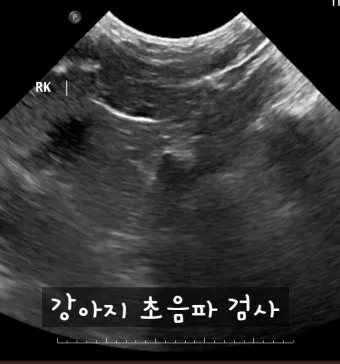

IRIS(International Renal Interest Society, 국제 신장 학회)에 따르면, 강아지 신부전은 1기부터 4기까지 총 4단계로 나뉘어 있습니다. 2기는 신장 기능이 매우 소폭 저하되어 큰 증상이 없는 단계예요.